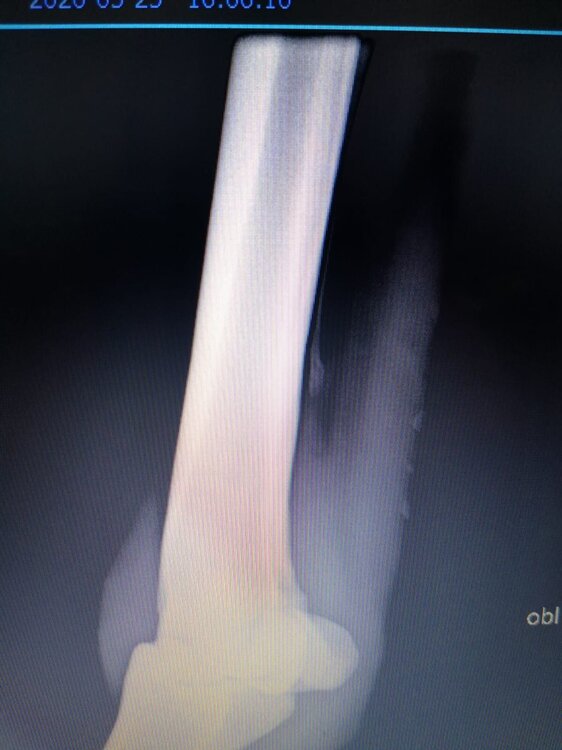

Salve volevo chiedervi qualche informazione in merce tò a un problema che ho avuto con la mia puledra. Qualche settimana fa mentre stavo lavorando alla corda è scivolata urtato l'arto posteriore sinistro. Arrivati in box ho messo dell'acqua a pressione perché si era gonfiato sia il nodello sia il pastorale. Già l'indomani l'arto era sgonfio ritornato normale, quindi ho continuato a lavorarla. Ma dopo qualche giorno di lavoro alla corda leggerissimo, al rientro in box ho notato che sia il nodello che il posturale gonfiavano nuovamente. Allora ho chiamato il veterinario che ha detto che la cavalla aveva una lussazione e mi ha insegnato come cura una fasciatura con della creta per 24h per cinque giorni e un antinfiammatorio. Dopo un paio di giorni la fasciatura ha fatto come delle vesciche e il gonfiore è aumentato dal pastorale alla garra. Abbiamo chiamato un altro veterinario abbiamo fatto vedere anche a lui la cavalla e diceva che poteva essere la frattura del ditino, ma si dovevano fare le lastre per essere sicuri. Ora abbiamo fatto le lastre e il radiologo dice che c'è dell'infiammazione ma non c'è niente di grave. Il veterinario,viste le lastre dice che deve essere operata. Allora abbiamo consultato un'altro veterinario che dice che la cavalla non ha assolutamente niente. Ora io vi allego le radiografie, datemi un vostro parere perché non só più cosa fare. Grazie